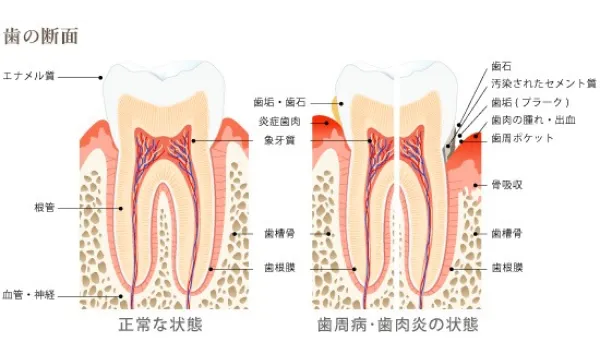

歯周病は、歯の周りの組織の病気です。 歯周病の原因である細菌に侵されると炎症は、 歯肉→歯と歯肉をつなぐ組織→歯と骨をつなぐ組織→骨というように進行していきます。 右に向かうほど炎症が強いといえます。

歯周病の初期の段階は歯肉炎と言います。歯肉炎では、歯周病菌が歯と歯肉の間に入り込み、プラークや歯石がたまりはじめます。 歯肉炎が進むと、歯と歯肉の間に歯周ポケットができて歯周ポケットにプラークや歯石がたまってきます。この状態を放置すると、歯周ポケットが深くなり、歯肉が腫れたり、出血するようになります。 そして、さらに歯周病が進行すると、歯槽骨が溶けはじめ、歯が支えられなくなります。最終的には歯が抜けてしまうことになります。皆様の大切な歯を守るためには、初期の段階から治療や正しいケアが必要です。

歯周病治療を行った結果、炎症がコントロールされた状態とは、炎症がなくなり(歯肉からの出血がなくなり)、最近との共生関係が確立(細菌がいなくなるのではなく影響がなくなる)その環境が永続しやすいような状態(浅いポケット)になることです。 残念ながらそれは、以前のように歯の間が歯肉に満たされ、骨が上まである状態ではありません。吸収してしまった骨は基本的には元には戻らず、歯肉は下がった状態で安定します。図に書くと以下のようになります。

根の間に上まで歯槽骨があり、歯の間は歯肉で覆われています。

歯周病になると

骨は歯肉の中で吸収し、歯肉の中と外には歯石と歯垢がこびりつき、それに伴い歯肉は腫れあがっています。 この状態に対し、患者さんのブラッシングが解消、歯科医院側では歯石取りとみがき残した部分のクリーニング、場合によっては手術を行って磨きやすい環境に変えてそれを持続すると…。

治療によりコントロールできた状態

歯周病の状態に対し、患者さんのブラッシングが解消、歯科医院側では歯石取りとみがき残した部分のクリーニング、場合によっては手術を行って磨きやすい環境に変えてそれを持続すると、このように変わります。 つまり、歯肉は腫れがなくなり、溶け続けていた骨は安定して固まり、骨の2~3ミリ上に歯肉が炎症が無い状態です。残念ながら、骨も歯肉も増殖せず、元の位置に回復とはいきません。これが歯周病からの治癒像です。 事故で手や足がなくなった人が再生しないのと同じように、これが現在の限界なのです。